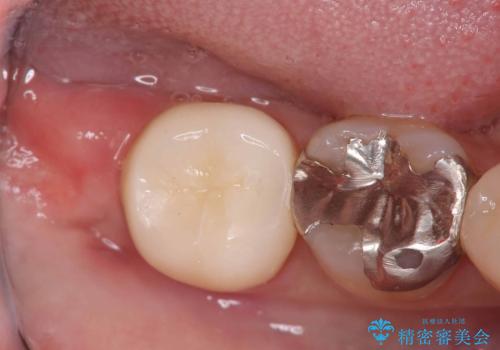

銀歯の下の虫歯|オールセラミッククラウン|歯を長持ちさせるための治療|歯の神経を守る

担当医 河野豊嘉